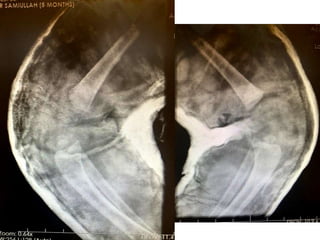

Phase-3: 2 marks

If the candidate orders some

investigations such as X-Ray show

him the X-Ray (and not the report)

and ask him:

1. What do you find on X-

Ray?

2. How will you proceed

further?

If the candidate reads X-Ray

correctly, draw referral lines and

request additional imaging show him

and ask why

CT / MRI

Phase-3: 2 marks Ifthe candidate orders some investigations such as X-Ray show him the X-Ray (and not the report) and ask him: 1. What do you find on X- Ray? 2. How will you proceed further? If the candidate reads X-Ray correctly, draw referral lines and request additional imaging show him and ask why CT / MRI